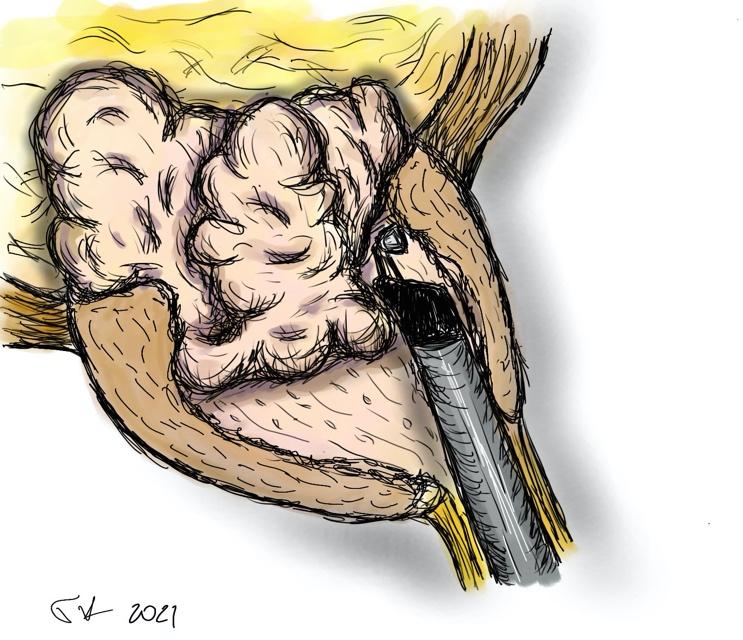

- το προστατικό αδένωμα αποκολλάται από την κάψα με τη βοήθεια του ειδικού ηλεκτροδίου εκπυρήνισης (εικόνες 1-4)

- το αδένωμα έχει πλέον αποκολληθεί από την προστατική κάψα και προωθείται στην ουροδόχο κύστη (εικόνες 5-6)

Εικόνες 1-4

εικόνες 5-6